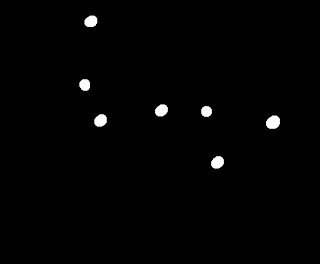

If we try to use the opening operation on this image again, we'll lose four of the cancer cells, leaving only one normal cell and one cancer cell. That's not good. Two dead normal cells are better that leaving the cancer cells behind undetected.

|

| The opening operator applied thrice on the binarized image. |